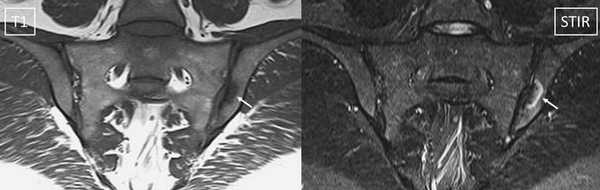

МРТ: двусторонний склероз подвздошной кости с сужением суставной щели (стрелка)